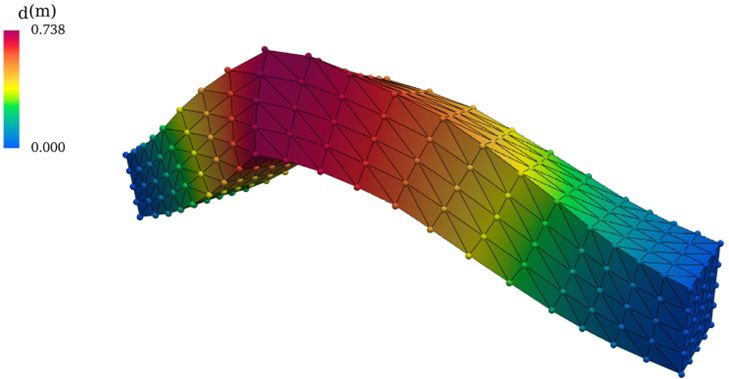

Mit der biomechanischen Simulation bildet das Team Abläufe im menschlichen Organismus nach – beispielsweise den Blutfluss. Dafür nutzt es segmentierte Bilddaten, erstellt Rechengitter (Meshes) und berechnet Materialeigenschaften wie Elastizität oder Viskosität. Auf dieser Basis können Ärzt*innen sowohl geometrische als auch simulationsbasierte Merkmale bestimmen. Dazu zählen etwa Gefäßdurchmesser oder mechanische Spannungen in Gefäßwänden.

Deformierter Balken als Beispiel für ein ML-basiertes Surrogat-Modell (Perceiver-IO) zur Lösung von Elastizitätsgleichungen. Die Punkte entsprechen den Surrogat-Vorhersagen, während die durchgezogenen Linien aus der exakten numerischen Simulation (FEM) stammen.